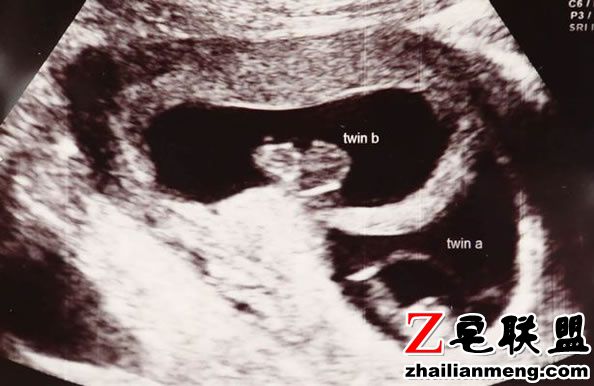

英国爱尔兰County Kilkenny 一对双胞胎出生相隔近3个月,姐姐Amy Elliott 急着与父母见面,在第23周时来到人世间。

而妹妹Katie Elliott 隔了87天后出生, 创下全世界出生时间相隔最远的纪录。